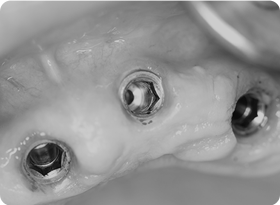

04임플란트 식립(2차수술)

뼈 이식재가 잇몸뼈로 전환된 걸 확인 후 임플란트를 이상적인 위치에 식립합니다.

05보철물장착

2차 수술 후 잇몸이 아문 다음 환자의 상태를 살펴본 후 보철물을 장착합니다.